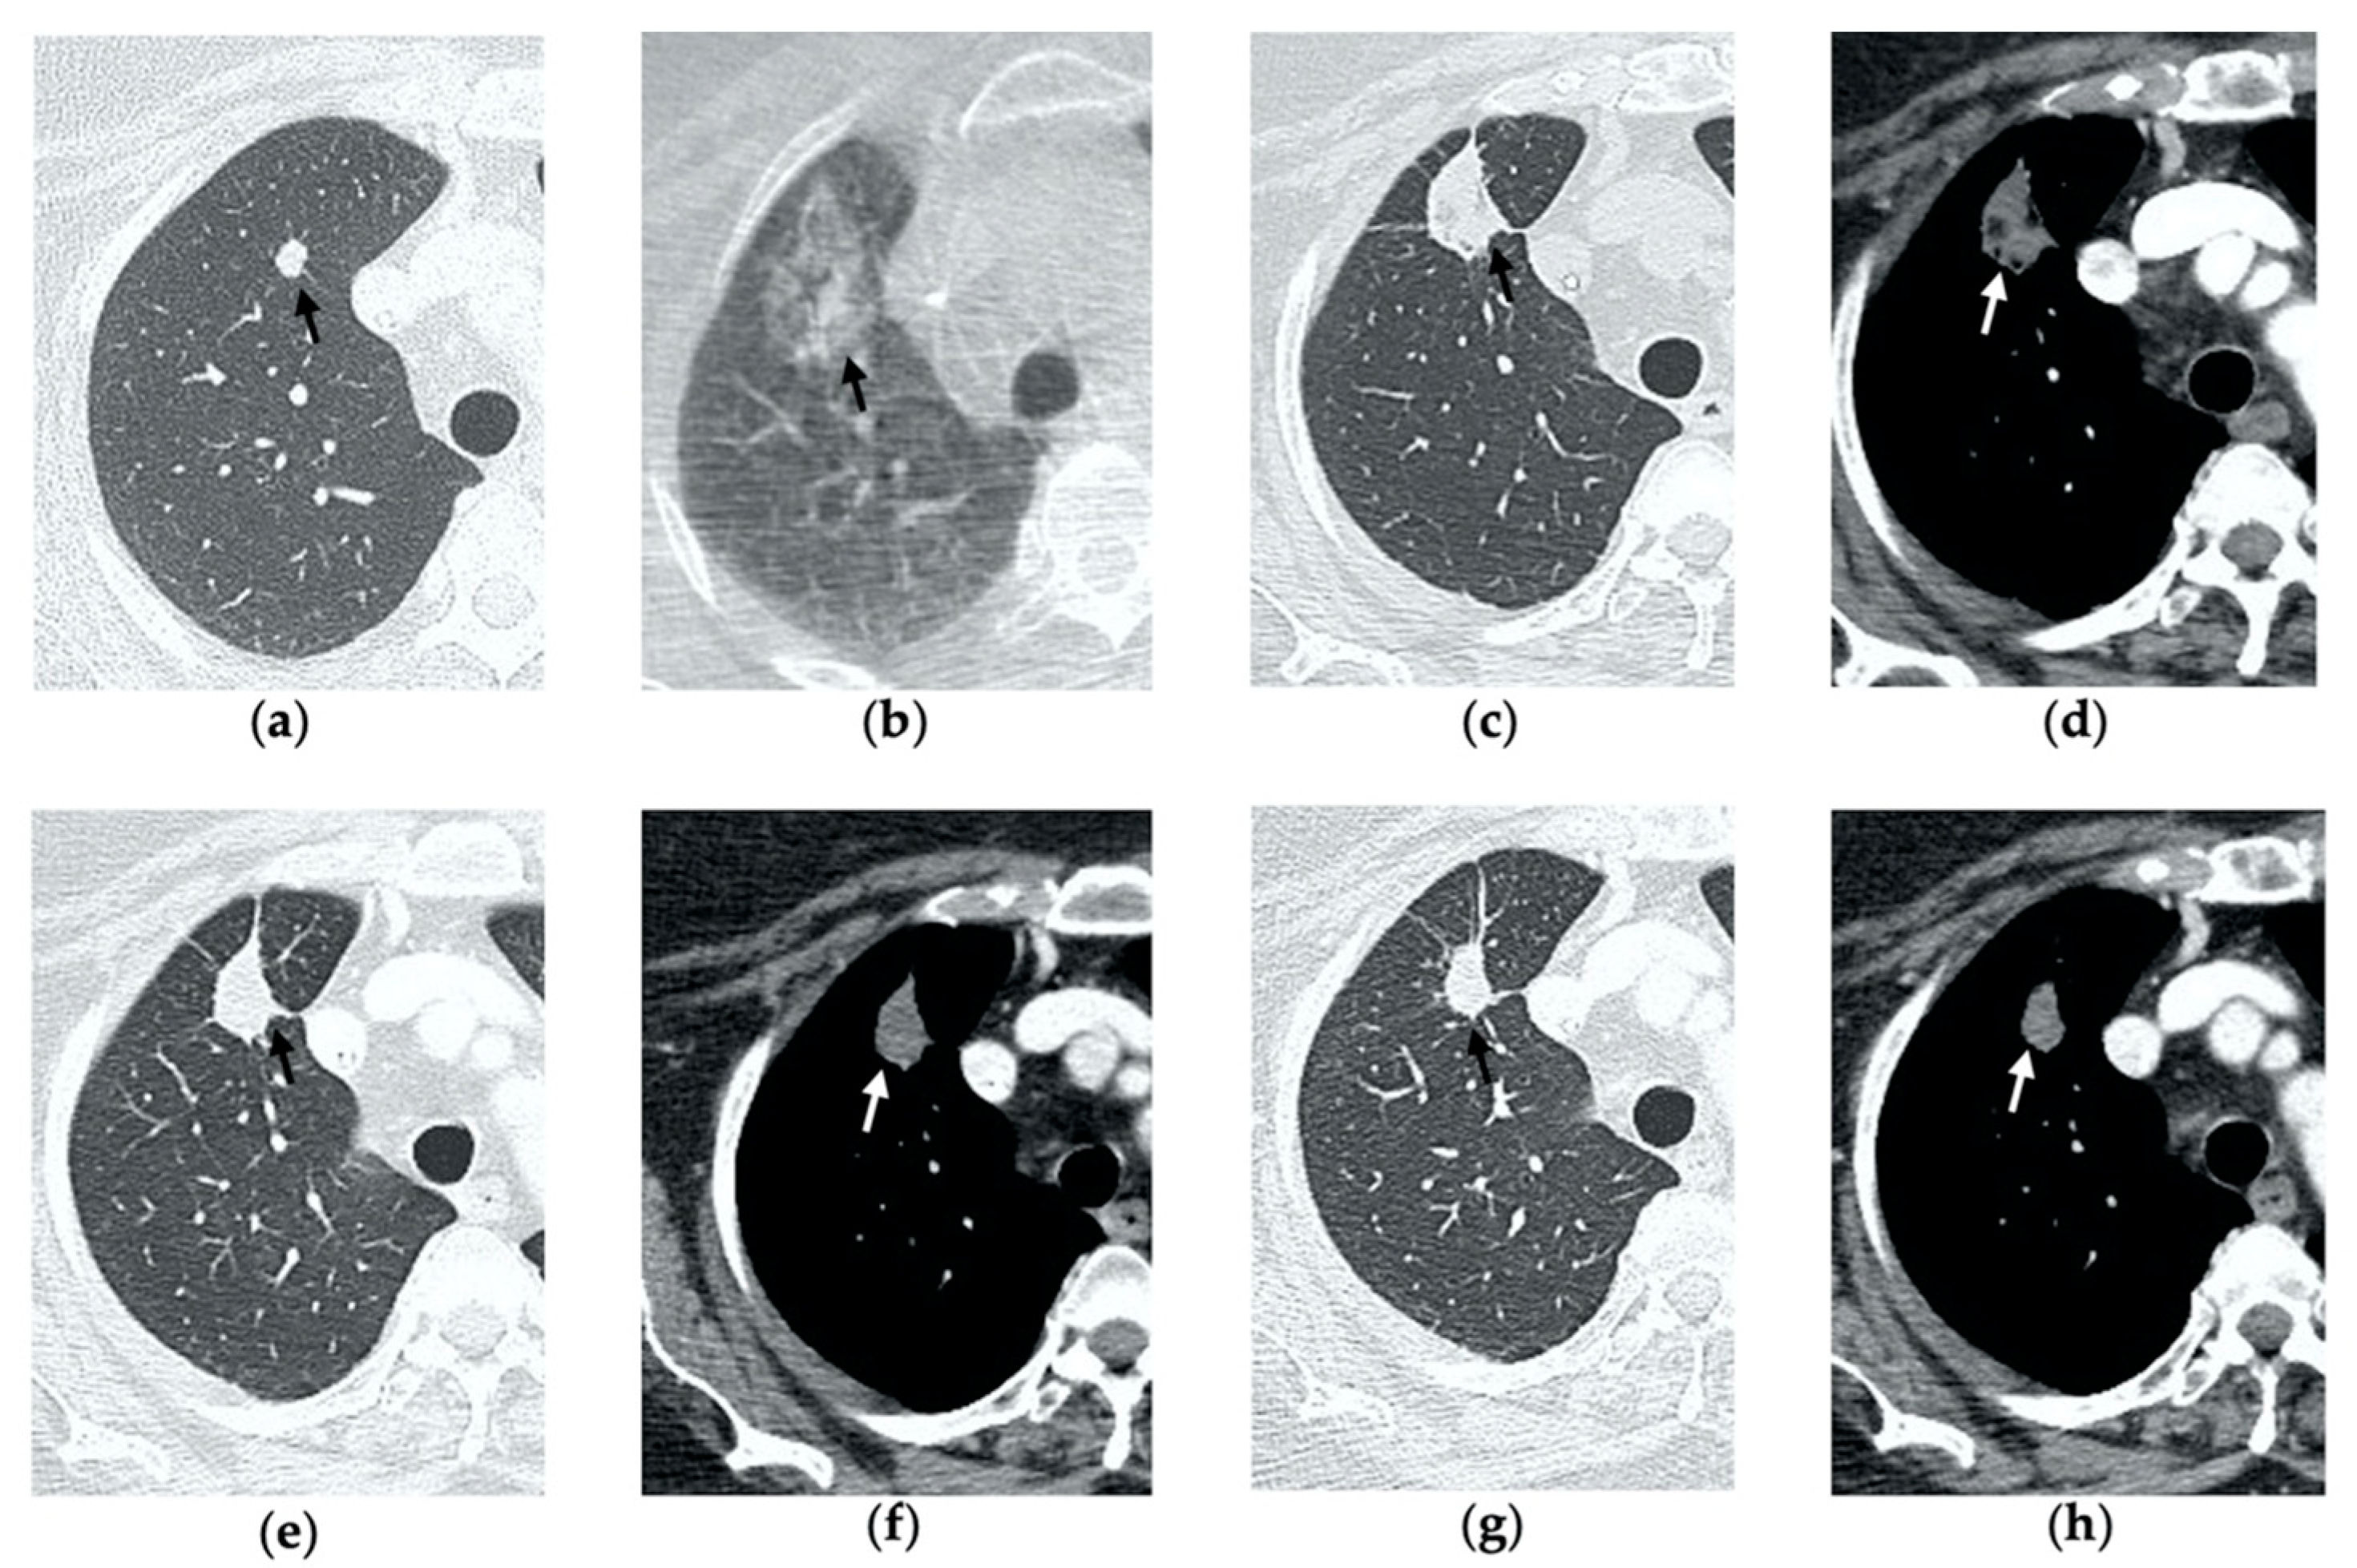

Figure 2. 69-year-old woman with a biopsy-proved NSCLC in the right upper lobe. (a) Pre-treatment axial CT. (b) Cone-beam CT image post-MWA shows GGO (black arrow) among the ablation site. (ce) Axial 1-month follow-up CT shows (c) a large consolidation with well-defined margins, inner hypoattenuating bubbles and a cavitation (black arrow) in communication with a peripheral bronchus (arrowhead); (d) on a different level, central necrotic material is seen within the cavitation (black arrow) (e) with no contrast enhancement (white arrow). (f,g) Axial 6-month follow-up CT images show resolution of the cavitation and decrease in size of the consolidation (black arrow) with no contrast material uptake (white arrow). (h,i) Axial 9-month follow-up CT image shows a linear fibrotic band with no contrast enhancement.

3.2. Contrast-Enhanced CT at 1 Month

By the first month after MWA, the rim of parenchymal GGO has dissolved in most patients as a result of regressing parenchymal edema, inflammation and hemorrhage, and the ablation site appears as an area of consolidation with a mean diameter still larger than the preablation zone (Figure 3c,d and Figure 4c,d) [21]. It is, therefore, crucial in this phase to measure the area of consolidation by its maximum axial diameter in order to thoroughly compare it during the following phases [7]. The consolidation may demonstrate inner cavitation or a central hypoattenuating area with reduction in contrast material uptake, along with a mild peripheral enhancement layer as an expression of reactive hyperemia, which should present smooth with linear margins (Figure 1c) [7,15]. This phenomenon must be referred to benign periablational enhancement and it should be differentiated from pathological contrast uptake, which is usually more irregular and nodular-shaped [7]. It is, therefore, pivotal to perform CT before and after contrast material administration in order to adequately evaluate the enhancement features of the treated tumor. The ablation site may also show hypoattenuating bubbles or a cavity with thin walls, containing solid tissue with reduced contrast enhancement, necrotic material or air-fluid levels, and a communication between the cavitation and a bronchus may be recognized (Figure 2c–e) [7,16]. The latter being a common finding since the necrotic tissue may be evacuated through a bronchus and it should not be mistaken for rare although possible complications, such as an abscess or a broncho-pleural fistula (BPF). Unlike the normal cavitary changes of the ablation area, an abscess is a rare complication (0.5%) [20] and appears as a cavity with thick walls, irregular internal contours and air-fluid level, and must be suspected when fever and laboratory signs of infection are present [22]. Pleural changes are also common findings, especially in peripheral lesions, including pleural thickening in the region of pleura traversed by the microwave antenna, pleural retraction and effusion [15]. Reactive mediastinal lymphadenopathy often occurs at an early stage, and it should not be considered a sign of tumor progression [7,23].

3.4. Contrast-Enhanced CT at 6 Months

After 6 months, the ablation site undergoes further involution and there should not be any inner contrast enhancement, except for the persistent benign periablational area (Figure 2f,g) [7]. The previously mentioned cavities decrease in size and may completely disappear. CT images may show fibrotic scarring without contrast enhancement and mild architectural parenchymal distortion of the surrounding lung (Figure 1f,g) [24]. At this stage, small treated nodules may already show a linear fibrotic evolution on CT images (Figure 2h,i).